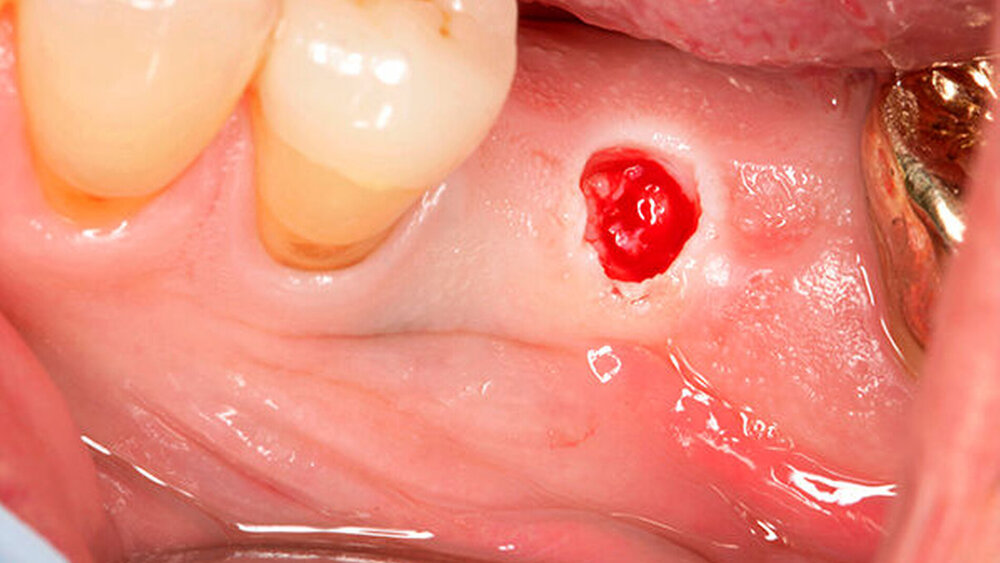

Die größte Herausforderung dabei, trotz 3D-Planung und Bohrschablone, ist es, die rote Ästhetik im Frontzahnbereich zwei bis drei Monate nach der Freilegung vorhersagbar zu kalkulieren. Da spielen viele Einflussfaktoren eine Rolle, eine zu dünne vestibuläre Knochenlamelle, der Stressfaktor „axiale Bewegung“, der diese dünne Knochenlamelle schnell überfordern kann etc. Zieht sich das rosafarbene Volumen zurück, ist das natürlich für den Zahntechniker schwierig zu handeln. Eine rosafarbene Gingivakappe, die aus Keramik aufgebrannt wird, kann helfen. Das ist zwar ein Kompromiss, aber ein Kompromiss, mit dem die Patienten leben können.

Was wäre die Alternative?

Wilde:

Aufwendige Augmentationen. Nach umfangreichen Knochendefekten im anterioren Bereich müsste der Knochen aufgebaut werden, Bindegewebstransplantate etc. verbessern die Situation weiter. Doch Patienten möchten irgendwann auch einmal die Behandlung abschließen. Und Zahntechniker meistern die keramische Gingivakorrektur wirklich großartig. Auch wenn es für den Behandler wenig zufriedenstellend ist, es gilt mit adäquatem Aufwand ein gutes Ergebnis zu erzielen.